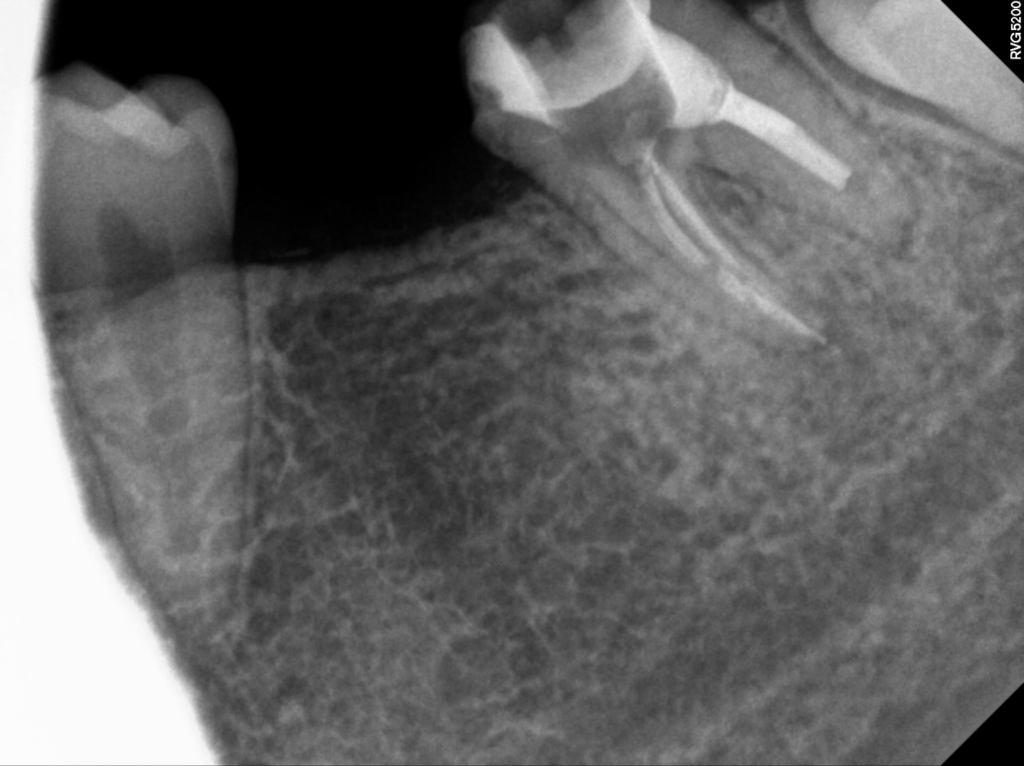

24.10.17

이 환자분은 내원 당시 임상적으로는 분명한 불편 증상이 있었지만, 방사선 사진을 확인한 결과 다행히도 뚜렷하게 크게 퍼진 병변은 아직 나타나지 않은 상태였습니다.

증상 경과와 과거 신경치료 이력을 먼저 확인한 뒤 정밀 촬영을 진행했고, 조사된 내용을 토대로 재근관치료가 필요한 이유를 환자분께 차근차근 안내드렸습니다. 충분한 설명 후 치료 방향에 대한 동의를 얻어 재치료 절차를 시작하게 되었습니다.